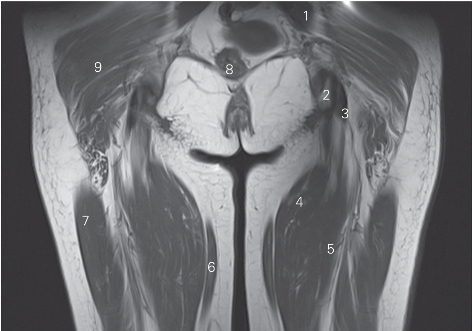

图5-17 经坐骨结节的冠状断层MR T1加权图像

1 臀中肌 gluteus medium 2 坐骨结节 ischial tuberosity

3 半膜肌腱 tendon of semimembranosus 4 半腱肌 semitendinosus

5 半膜肌 semimembranosus 6 股薄肌 gracilis

7 股外侧肌 vastus lateralis 8 直肠 rectum

9 臀大肌 gluteus maximus